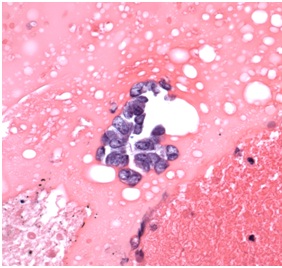

Microscopic examination of a third excisional biopsy performed three weeks later proved positive for a malignant neoplasm. Neoplastic cells were noted to infiltrate into the surrounding fibroadipose tissue in a sheet-like arrangement (Figure I)

Figure 1: Skin Biopsy (20x). The Images Show Nests And Solid Sheets Of Neoplastic Cells Infiltrating Into The Surrounding Fibroadipose Tissue. The Neoplastic Cells Also Contained Large Hyperchromatic Nuclei And Finely Granular Nuclear Chromatin.

Their nuclei were large, hyperchromatic, and contained finely granular nuclear chromatin. The neoplastic cells were immunoreactive with chromogranin, synaptophysin, and cytokeratin 20 (CK 20). CK 20 stained positively in a paranuclear “dot-like” pattern (Figure 2C) the neoplastic cells did not stain with cytokeratin 7 (CK 7), thyroid transcription factor-1 (TTF-1), S-100 protein, or melan-A/mart1. The histopathologic features and immunohistochemical-staining pattern were felt to be diagnostic for primary cutaneous MCC. Accordingly, the patient underwent external-beam radiation and was treated with chemotherapy based on the regimen for small cell carcinoma of lung.